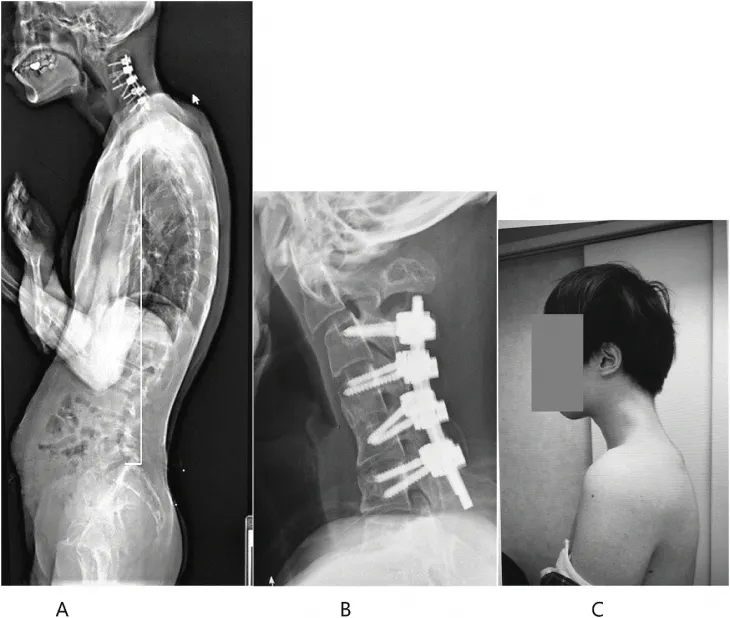

거의 ‘ㄱ’자 형태로 심하게 꺾인 목, 뿔처럼 튀어나온 목뼈.

일본 규슈 오이타현의 오이타 정형외과를 찾은 남성 환자(당시 25세)는 한눈에 봐도 그 상태가 심각했다.

환자는 병원을 찾기 전 6개월 동안 심한 목 통증을 겪고 있었으며 고개를 들어 올릴 수 없다고 호소했다. 목이 너무 심하게 꺾여 그의 턱은 가슴에 거의 맞닿아 있었다.

정밀검사를 진행한 결과 목뼈가 왜곡되고 탈구됐으며, 시간이 지나면서 척추(특히 경막) 부위에 흉터 같은 조직이 증식한 것이 관찰됐다.

이에 의료진은 수술을 택했다. 먼저 척추뼈의 튀어나온 부분과 경막에 생긴 흉터 같은 조직 일부를 제거했다.

이후 목뼈에 나사와 금속 막대를 삽입해 자세를 교정했다.

수술 후 6개월 만에 환자는 머리를 수평으로 쉽게 유지할 수 있게 됐다. 그 결과 음식을 삼키는 어려움도 없어져 식사를 정상적으로 할 수 있게 됐고, 전반적인 자세와 삶의 질이 크게 개선됐다.